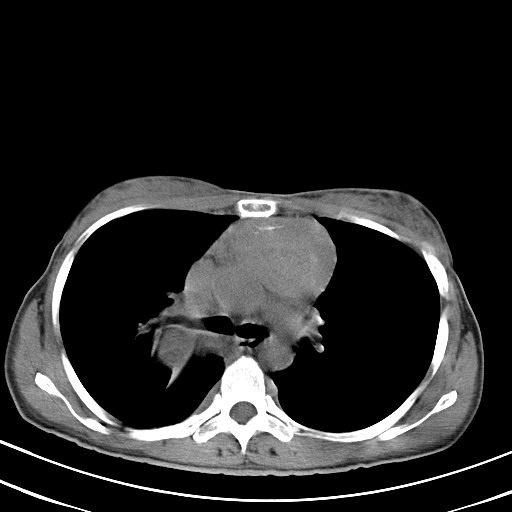

以下是引用汪涛同志在2007-8-2 0:40:00的发言:[br]病变虽然广泛,同时侵及双侧纵隔,但是无论左侧和右侧上下观察都是与右侧颈部甲状腺相延续的,而且强化幅度基本一致,又同时具有恶性病变病变的某些特征:肿块过大且密度不均,部分层面与正常纵隔结构分界不清,结合病史已有两年,考虑:胸内甲状腺肿恶变可能。[br]